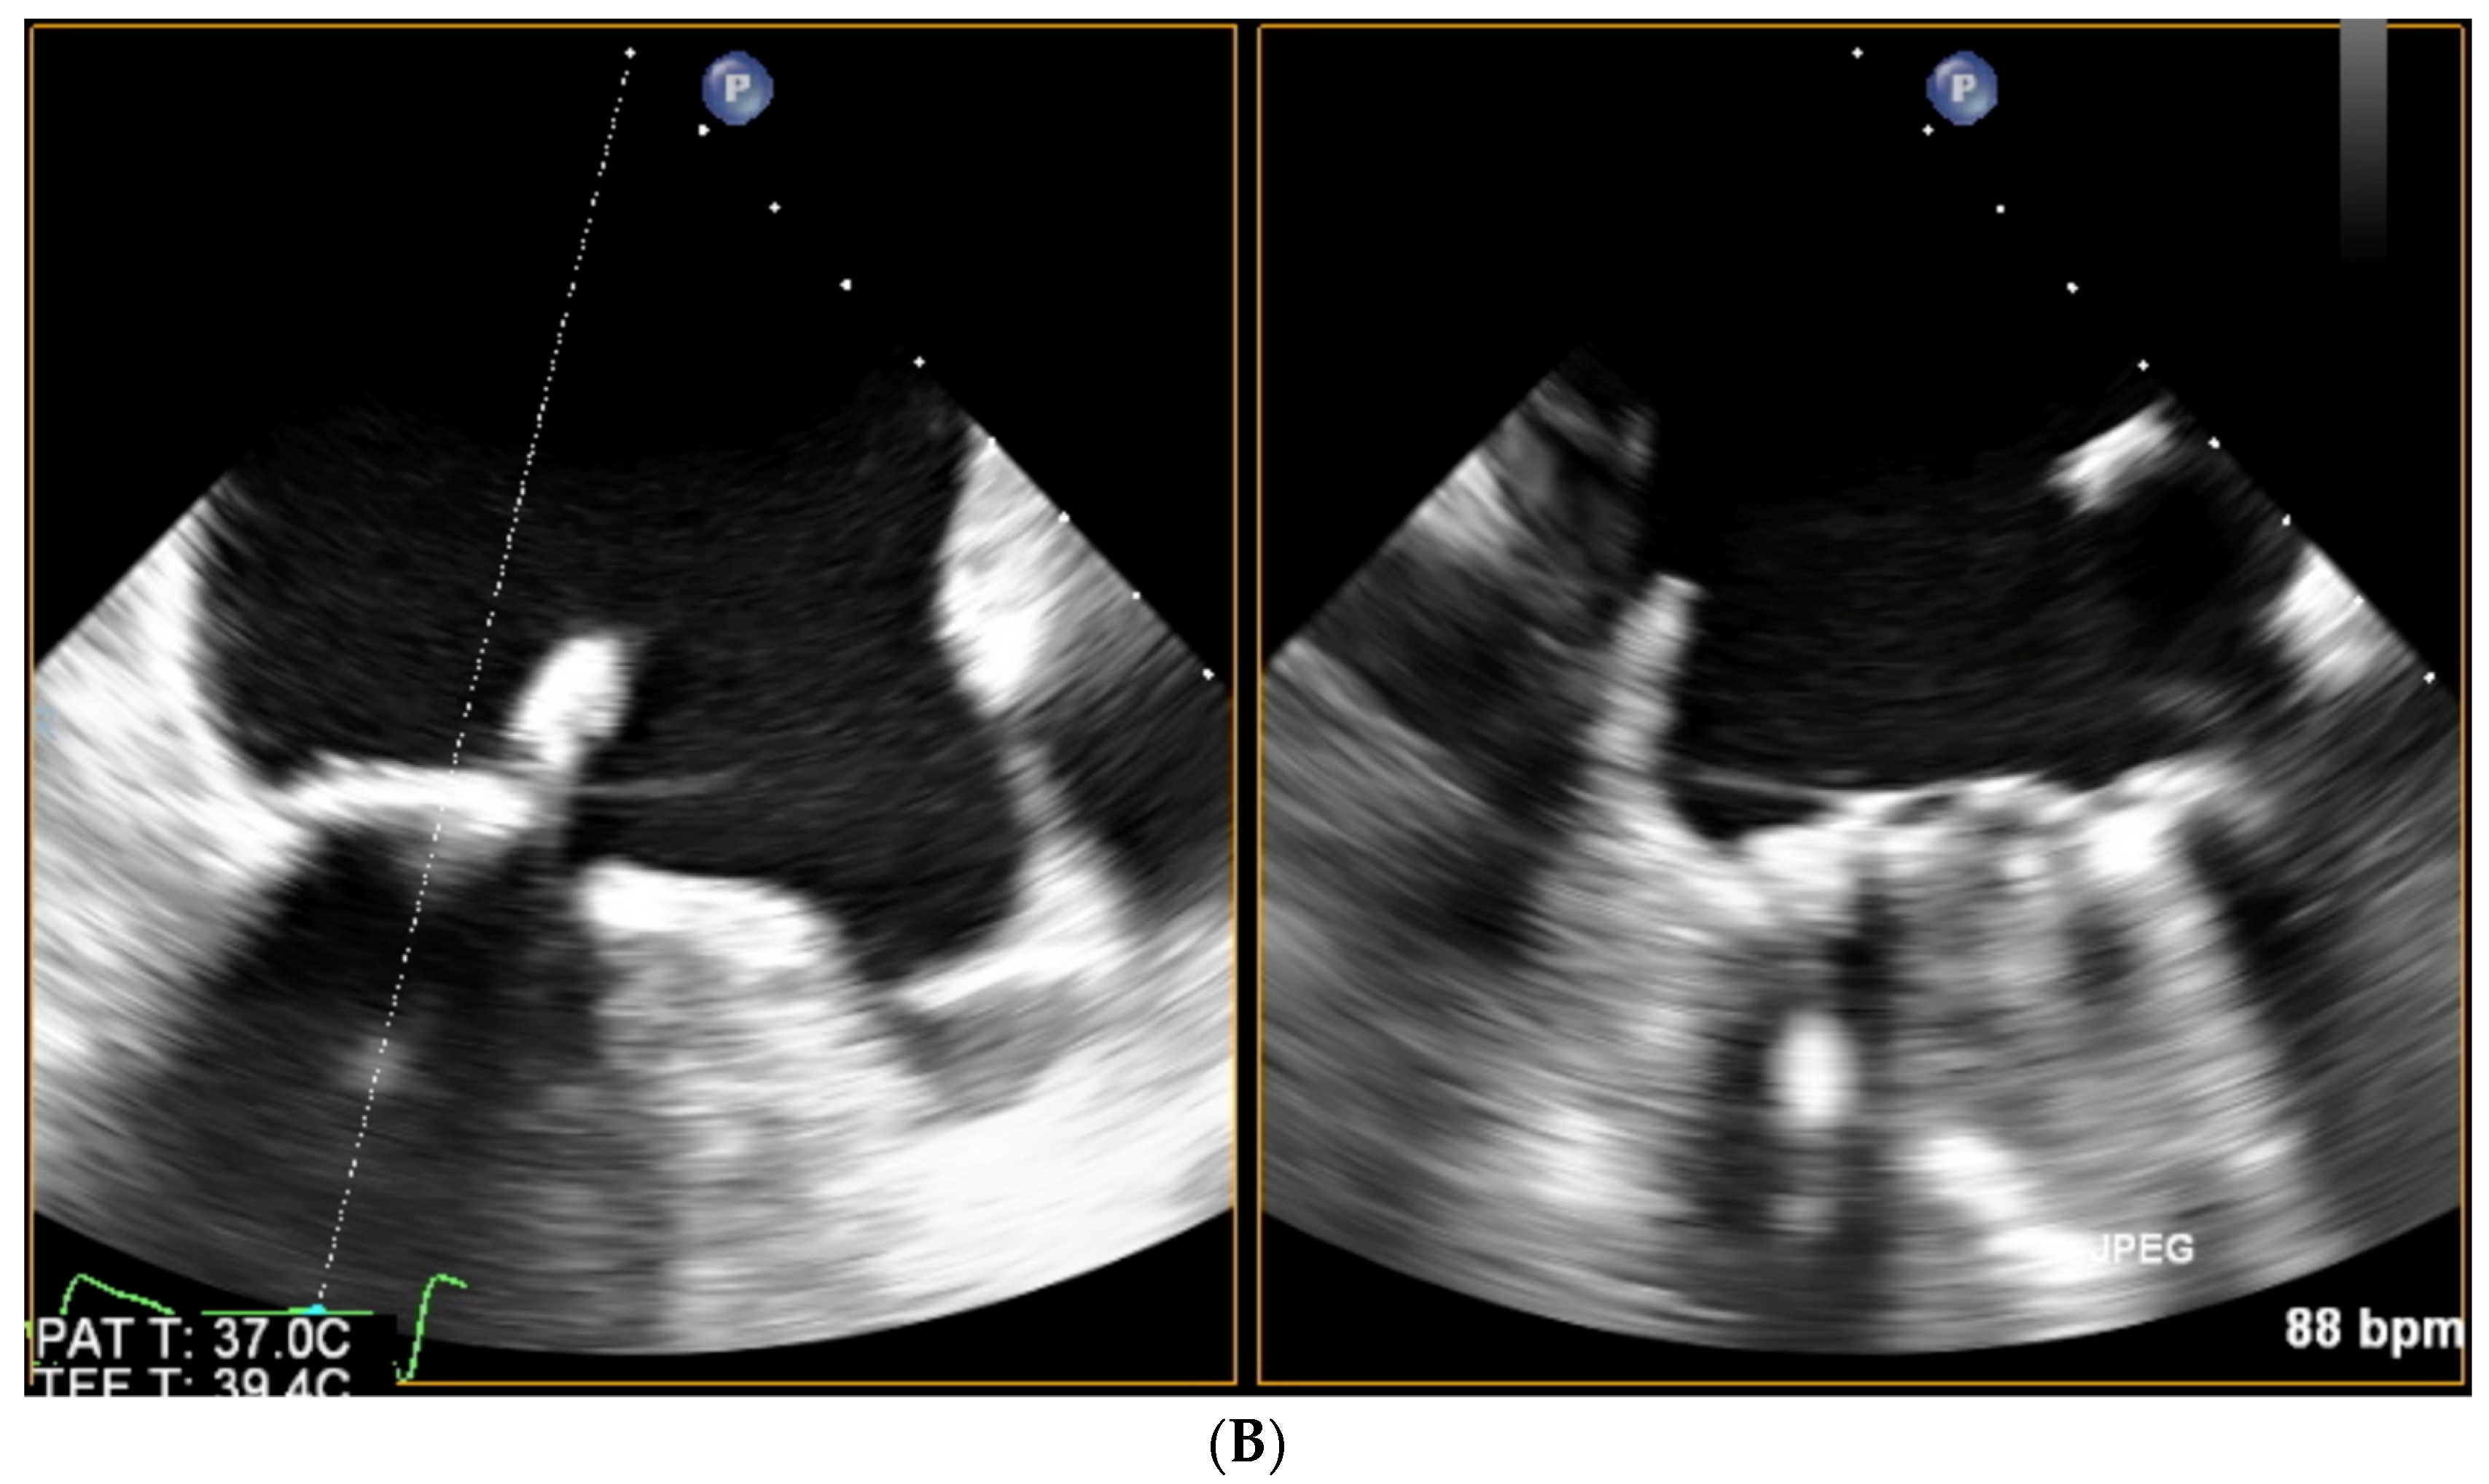

Paravalvular Leak Echo Imaging before and during the Percutaneous Procedure